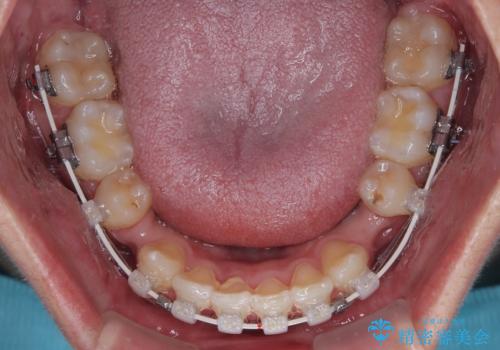

- 矯正装置

- 審美装置

矯正装置には白いプラスチックブラケットと白いコーティングワイヤーを使用し、見た目にも配慮した治療を行いました。